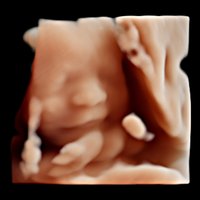

• Volume Master, Volume Advance, Live HQ, Auto NT (Geburtshilfe)

• 3D/4D-Modus